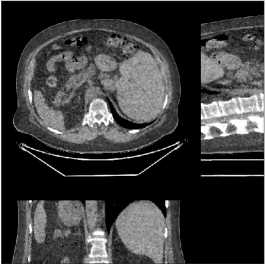

Fig.Β 5 shows the reconstructions and the corresponding error (magnitudes) images (shown for the central axial, sagittal, and coronal planes) for FDK, PWLS-EP, and PWLS-ULTRA () with the patch-based weights. Compared to FDK and PWLS-EP, PWLS-ULTRA significantly improves image quality by reducing noise and preserving structural details (see zoom-ins). Fig.Β 6 shows the RMSE for each axial slice in the PWLS-EP and PWLS-ULTRA (with the weights ) reconstructions. PWLS-ULTRA clearly provides large improvements in RMSE for many slices, with greater improvements near the central slice.

Section IV.E and Table III of [60] compared the performance of various methods for low-dose cone-beam (3D) CT reconstruction, for the XCAT phantom volume. Fig.Β 13 shows the reconstructions and the corresponding error (magnitudes) images (shown for the central axial, sagittal, and coronal planes) at for FDK, PWLS-EP, PWLS-ST (with ), and PWLS-ULTRA () with patch-based weights . PWLS-ULTRA provides better reconstructions and reconstruction errors compared to the conventional FDK and the non-adaptive PWLS-EP. PWLS-ULTRA also outperforms the proposed PWLS-ST scheme, and provides sharper reconstructions of image edges (see zoom-ins).